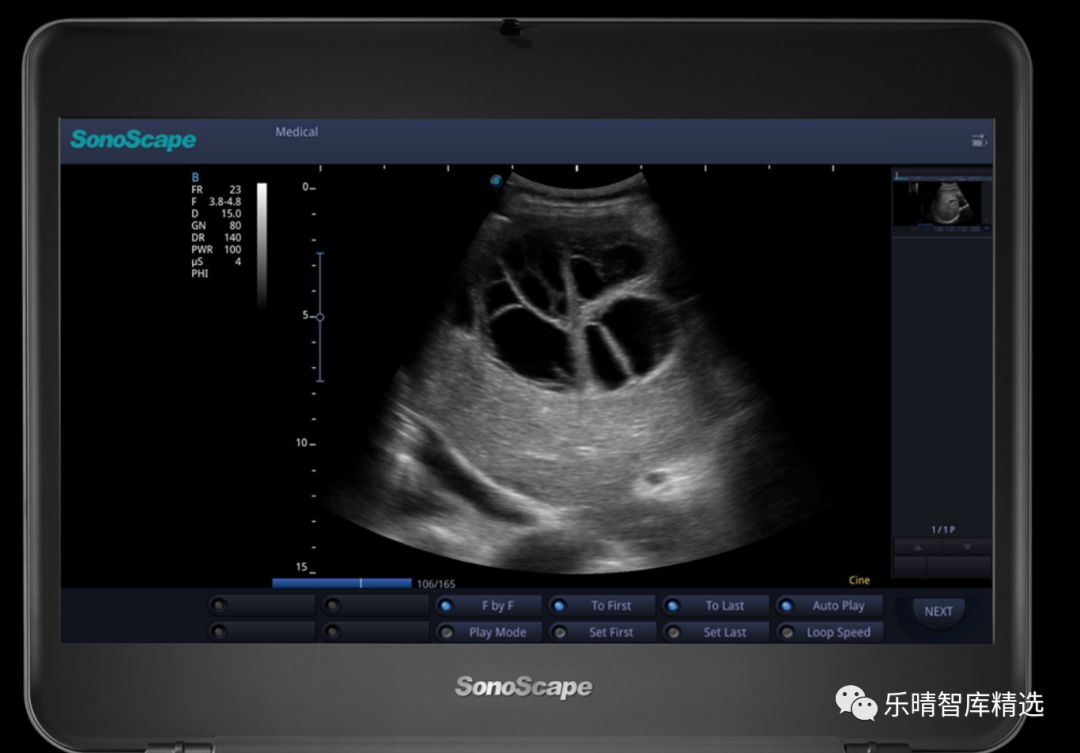

医用超声诊断仪最早诞生于20世纪60年代,早期只能获取人体组织的结构信息,简称B超,通过黑白的灰阶图像来显现不同组织对超声波的反射强度,因此又称为黑白超。

直到20世纪80年代,通过超声波的多普勒原理和技术,超声诊断仪不仅可以显示结构信息,还可以显示人体内的血流信息,并且通过红蓝两种颜色来区分血流的方向,彩超-彩色多普勒超声诊断仪正式诞生,彩超的时代正式到来(由于黑白超目前只占整个市场容量不到10%份额,因此下文中的超声多指彩超)。百度搜索“乐晴智库”获得更多行业报告。